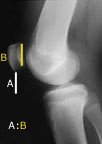

Two ratios have become standard in the assessment of patellar position - these are the Insall-Salvati and Blackburne-Peel vertical height ratios.

Insall-Salvati ratio - length of the patellar tendon (lowest pole of the patella to the tibial tubercle on X-ray) compared to the height of the patella - usually 1.02 +/- 0.2. A ratio of less than 0.8 is considered to be patella infera.

Blackburne-Peel ratio - lowest point on the patellar cartilage to the level of the tibial plateau compared to the length of the patellar articular surface - usually 0.54-1.06. A ratio of less than 0.54 is considered to be patella infera.

In 1991, (ref 2) two colleagues and I compared the two knees of 51 individuals and found that, although the ratio may vary slightly from person to person, it is remarkably consistent between the two knees of the same person. This allowed us to diagnose patella infera by comparing the ratio in the problem knee with that in the normal knee on serial lateral X-rays with the knee in 30-60° of flexion.